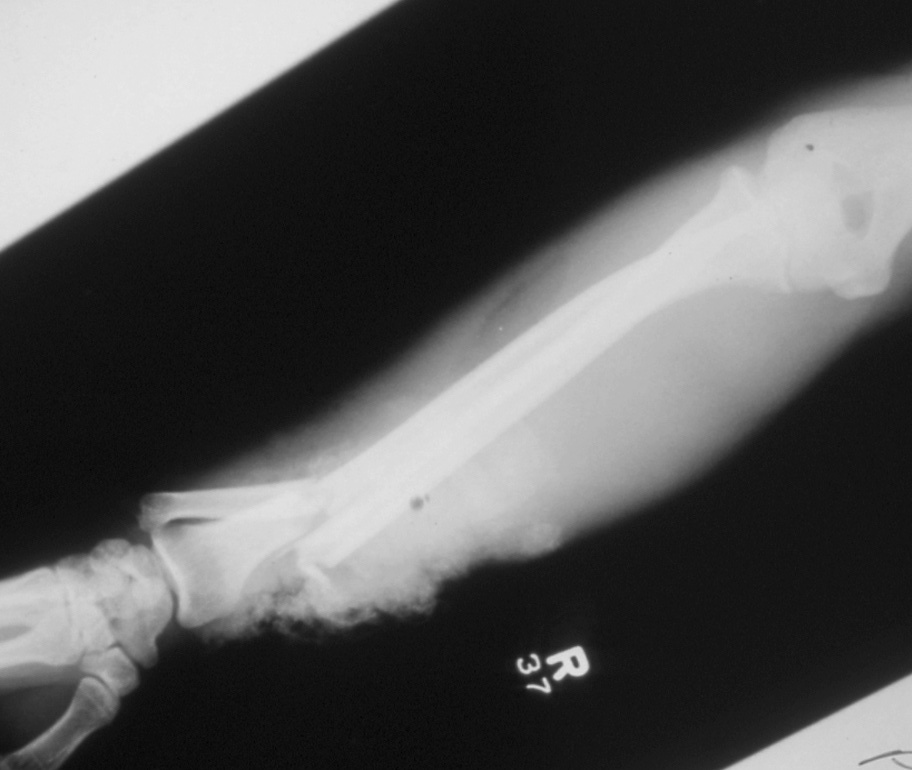

- Also known as a reverse Monteggia fracture or Piedmont fracture, the Galeazzi fracture is fracture of the middle to distal third of the radial shaft combined with a subluxation or dislocation of the DRUJ.8,11

- These injuries typically result from direct impact to the radius with forearm pronation. When a patient sustains a radial shaft fracture in the middle to distal third of the bone, suspicion should be raised for an associated DRUJ injury.1,8

- Radiology studies - X-ray

- Anteroposterior (AP) and lateral views are usually sufficient, but an oblique view may help to better classify the injury.

- If a coexistent injury is suspected, the distal wrist and proximal elbow should also be radiographed.